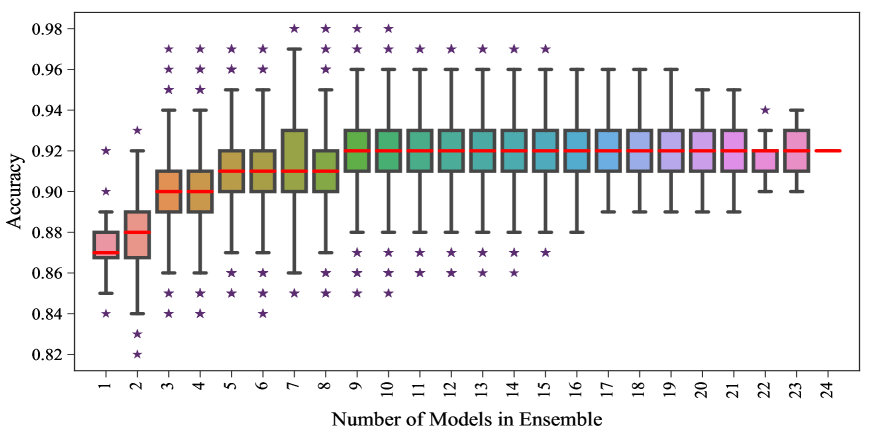

We trained four different instances of each of the DCNs, i.e, AlexNet, VGG-16, VGG-19, ResNet-50, ResNet-101 and ResNet-152, to detect cardiomegaly. Thus a total of networks were trained on the same training data. There are a number of ways to perform ensemble on the trained model. The methods include linear averaging, bagging, boosting, stacked regression [29] etc. Since, the number of images in the training dataset is only 564, which is far less than the number of trainable parameters in the classifiers, the individual classifiers always overfit the training set. In this situation, if bagging, boosting and/or stacked regression are employed to build the ensemble model, it will result in a completely biased model. Thus, the ensemble models were obtained by using simple linear averaging of the probabilities given by the individual models. The performance of the ensembles was measured using 50 cardiomegaly and 50 normal images for all the possible combinations of the trained individual models. The performance of these combinations is shown in Fig. 5 using boxplots. The horizontal red bars indicate the 50 percentile values and the spread of the blue boxes indicate the 25 and 75 percentile values. The black stars indicate extreme points in the data. It can be observed from the figure that, combinations of 7 to 10 models can achieve higher accuracy, however they have the largest spread. On the other hand, as number of models in the ensemble increases, the accuracy of the ensemble model converges to a certain value which for this experiment was .